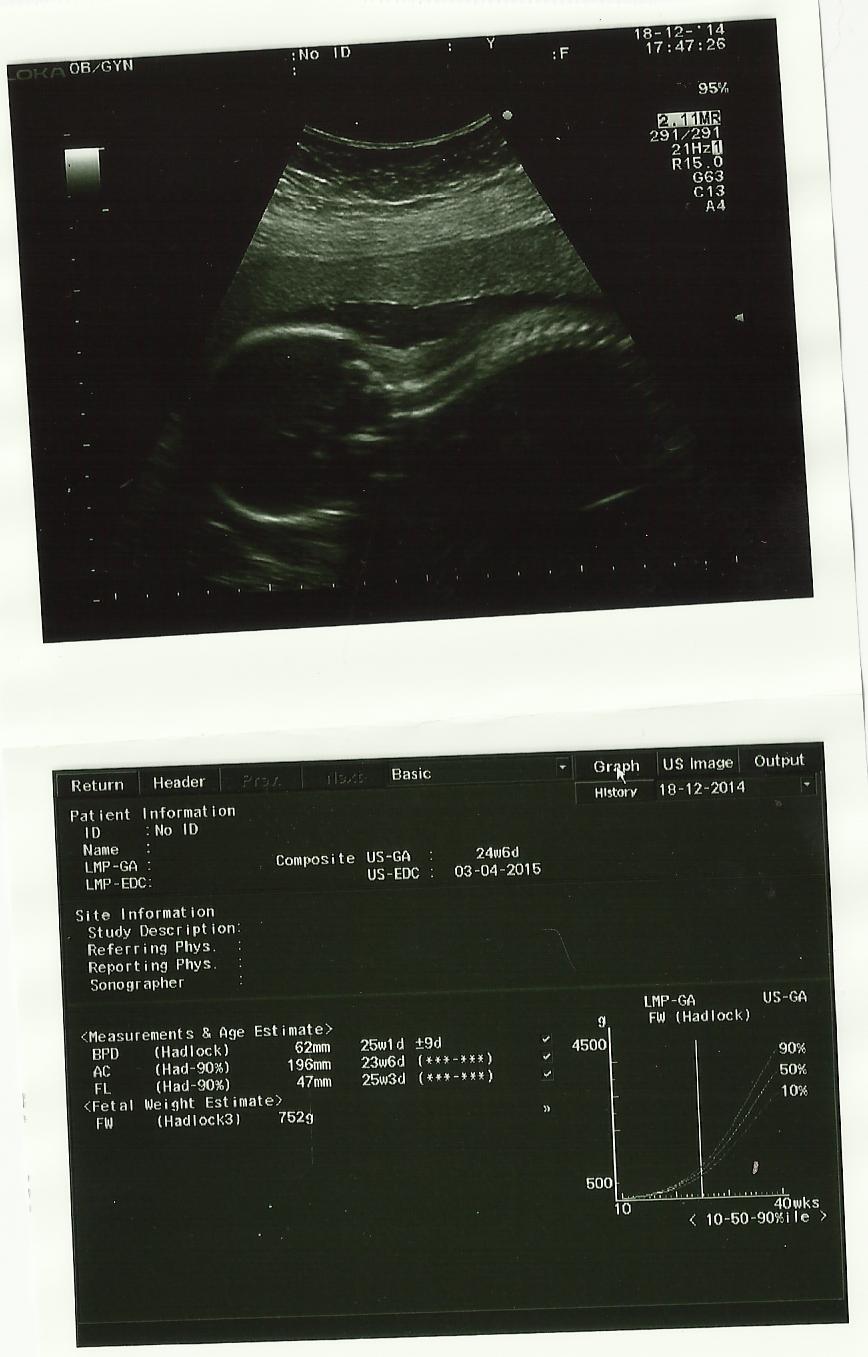

Op 18 december 2014 hadden mama en papa terug een afspraak bij dokter Lampaert.

Ondertussen ben jij 23 weken en 5 dagen… Je weegt ondertussen 750 gram en doet het goed! Mama en papa genieten met hoofdletter en voelen zich gezegend.

Ondertussen vertelt mama’s buik ook meer en meer dat jij eraan komt!

Je hebt deze echo terug wel geen zin om jou te laten zien. Wanneer de gynaecologe een foto neemt, draai jij je vlug zodat je met jouw rug naar ons komt te liggen. Onze gekke, lieve meid!